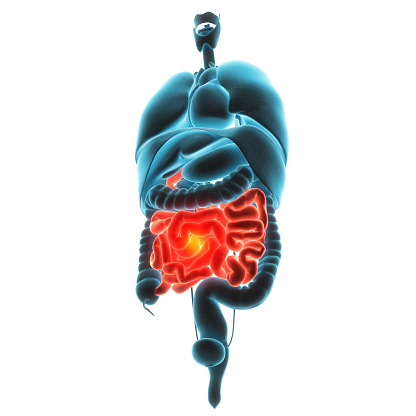

What causes overactive bowel? Symptoms, tests, and treatment

Having an overactive bowel means you have to make more frequent trips to the bathroom to relieve yourself. While this may sound abnormal in certain contexts, it may actually be absolutely ordinary for some. The general consensus over what constitutes normal bowel habits tends to be a single bowel movement every day, but this may ...click here to read more